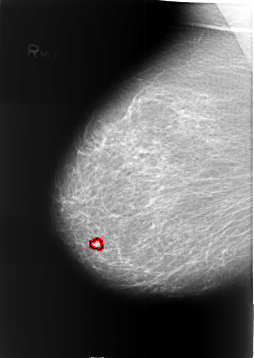

FILE: B_3391_1.RIGHT_CC.OVERLAY

TOTAL_ABNORMALITIES 1

ABNORMALITY 1

LESION_TYPE MASS SHAPE ROUND MARGINS CIRCUMSCRIBED

ASSESSMENT 2

SUBTLETY 3

PATHOLOGY BENIGN

TOTAL_OUTLINES 1

BOUNDARY